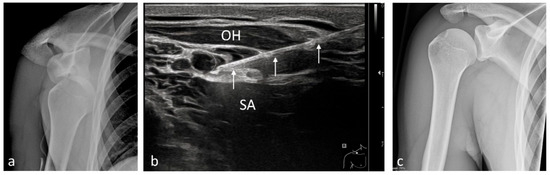

| Humerus | 148 | Brachial plexus block (supraclavicular)/10 (5)–20 |

| Shoulder | 99 | Brachial plexus block (interscalene)/3–5 |

| Shoulder prosthesis | 5 | Brachial plexus block (interscalene)/3–5 |

| Rotator cuff pathology | 63 | Brachial plexus block (interscalene)/3–5 |

| Shoulder osteoarthritis | 19 | Brachial plexus block (supraclavicular)/10 (5)–20 |